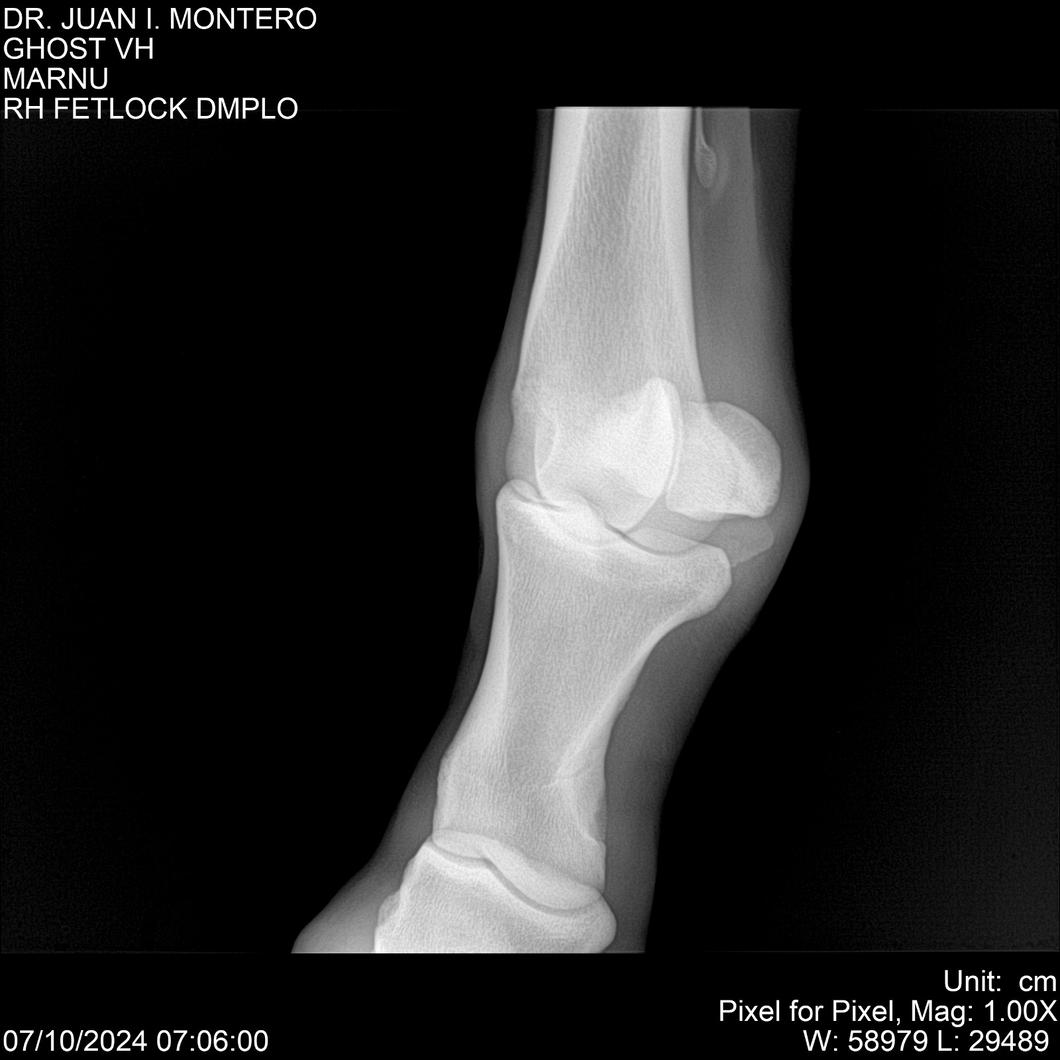

LOTE 15, GHOST VH 🔥 🔥 🔥 Lote Anterior Volver al remate Lote Siguiente Ficha Contacto Montevideo - Ficha del Lote Identificador: #282525 Categoría: Yeguarizos Montevideo - 69 Visualizaciones ClicData Contacto Empresa: Abelenda N. R., Walter Hugo Nombre*: Teléfono* : E-mail* : Mensaje Enviar Registrese gratis Este contenido Exclusivo está disponible sólo para usuarios registrados Ingresar